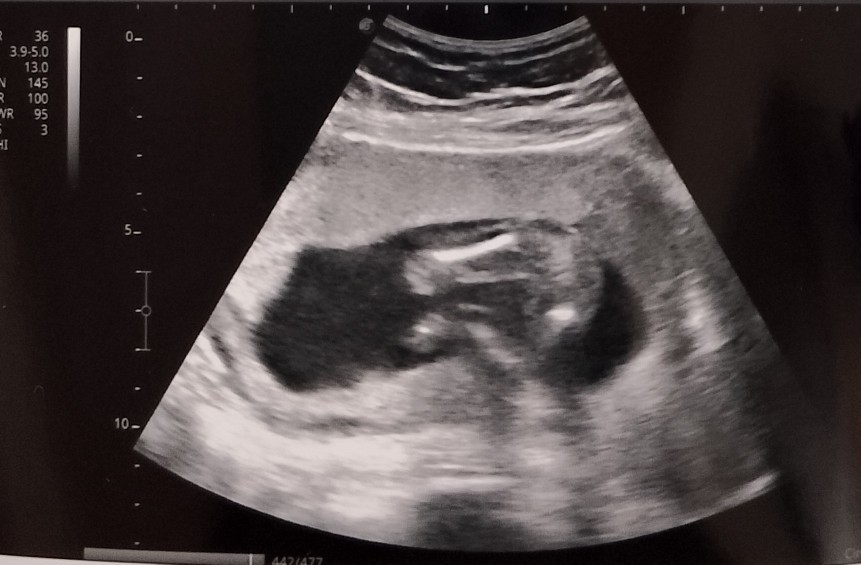

Baby's Gender Confused

here is my ultrasound and my ob gyn said the gender is female but I see it as a boy but not 100% sure. what do you think? TIA🫶 #Gender #babyboyorgirl #RespectMyPost #CuriousAlert #2ndtime

Sabi Kase mi pag daw may Nakita na parang burger, ibig sabihin girl po un. hehe

kitang kita Mami, Yung hiwa ni baby hehe